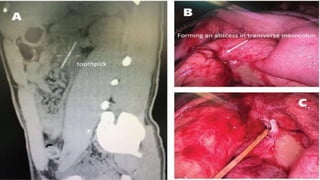

Male patient, 31 years old, admitted on April 15, 2016, with complaint of abdominal pain and vomiting for 3

consecutive days. The patient had a history of alcohol abuse and reported he might have accidentally

ingested a toothpick while drinking, 10 days prior to symptom presentation. Physical examination: vital

signs were stable, with mild upper abdominal tenderness and no rebound tenderness. WBC: 11.8×109/L

NEUT%: 82%, CRP: 54.4 mg/L. Abdominal contrast-enhanced computed tomography (CT) scans

demonstrated: a 62 mm long opaque foreign body at the third part of the duodenum, piercing the

transverse mesocolon and forming an abscess (4×3 cm), considered possibly to be a toothpick(Fig. 2A).

Emergency laparoscopy was conducted. Intraoperative exploration revealed upper abdominal adhesions.

Underneath the transverse colon, a mesentery encapsulated abscess was exposed with fibrin and pus on

the surface (Fig. 2B), where the penetrating wooden foreign body was identified as a toothpick (6 cm) (Fig.

2C). The toothpick was extracted and the wound was left open. An indwelling drainage tube was placed

during the surgical procedure. Five days post surgery the patient fully recovered and was discharged with

no further complications.